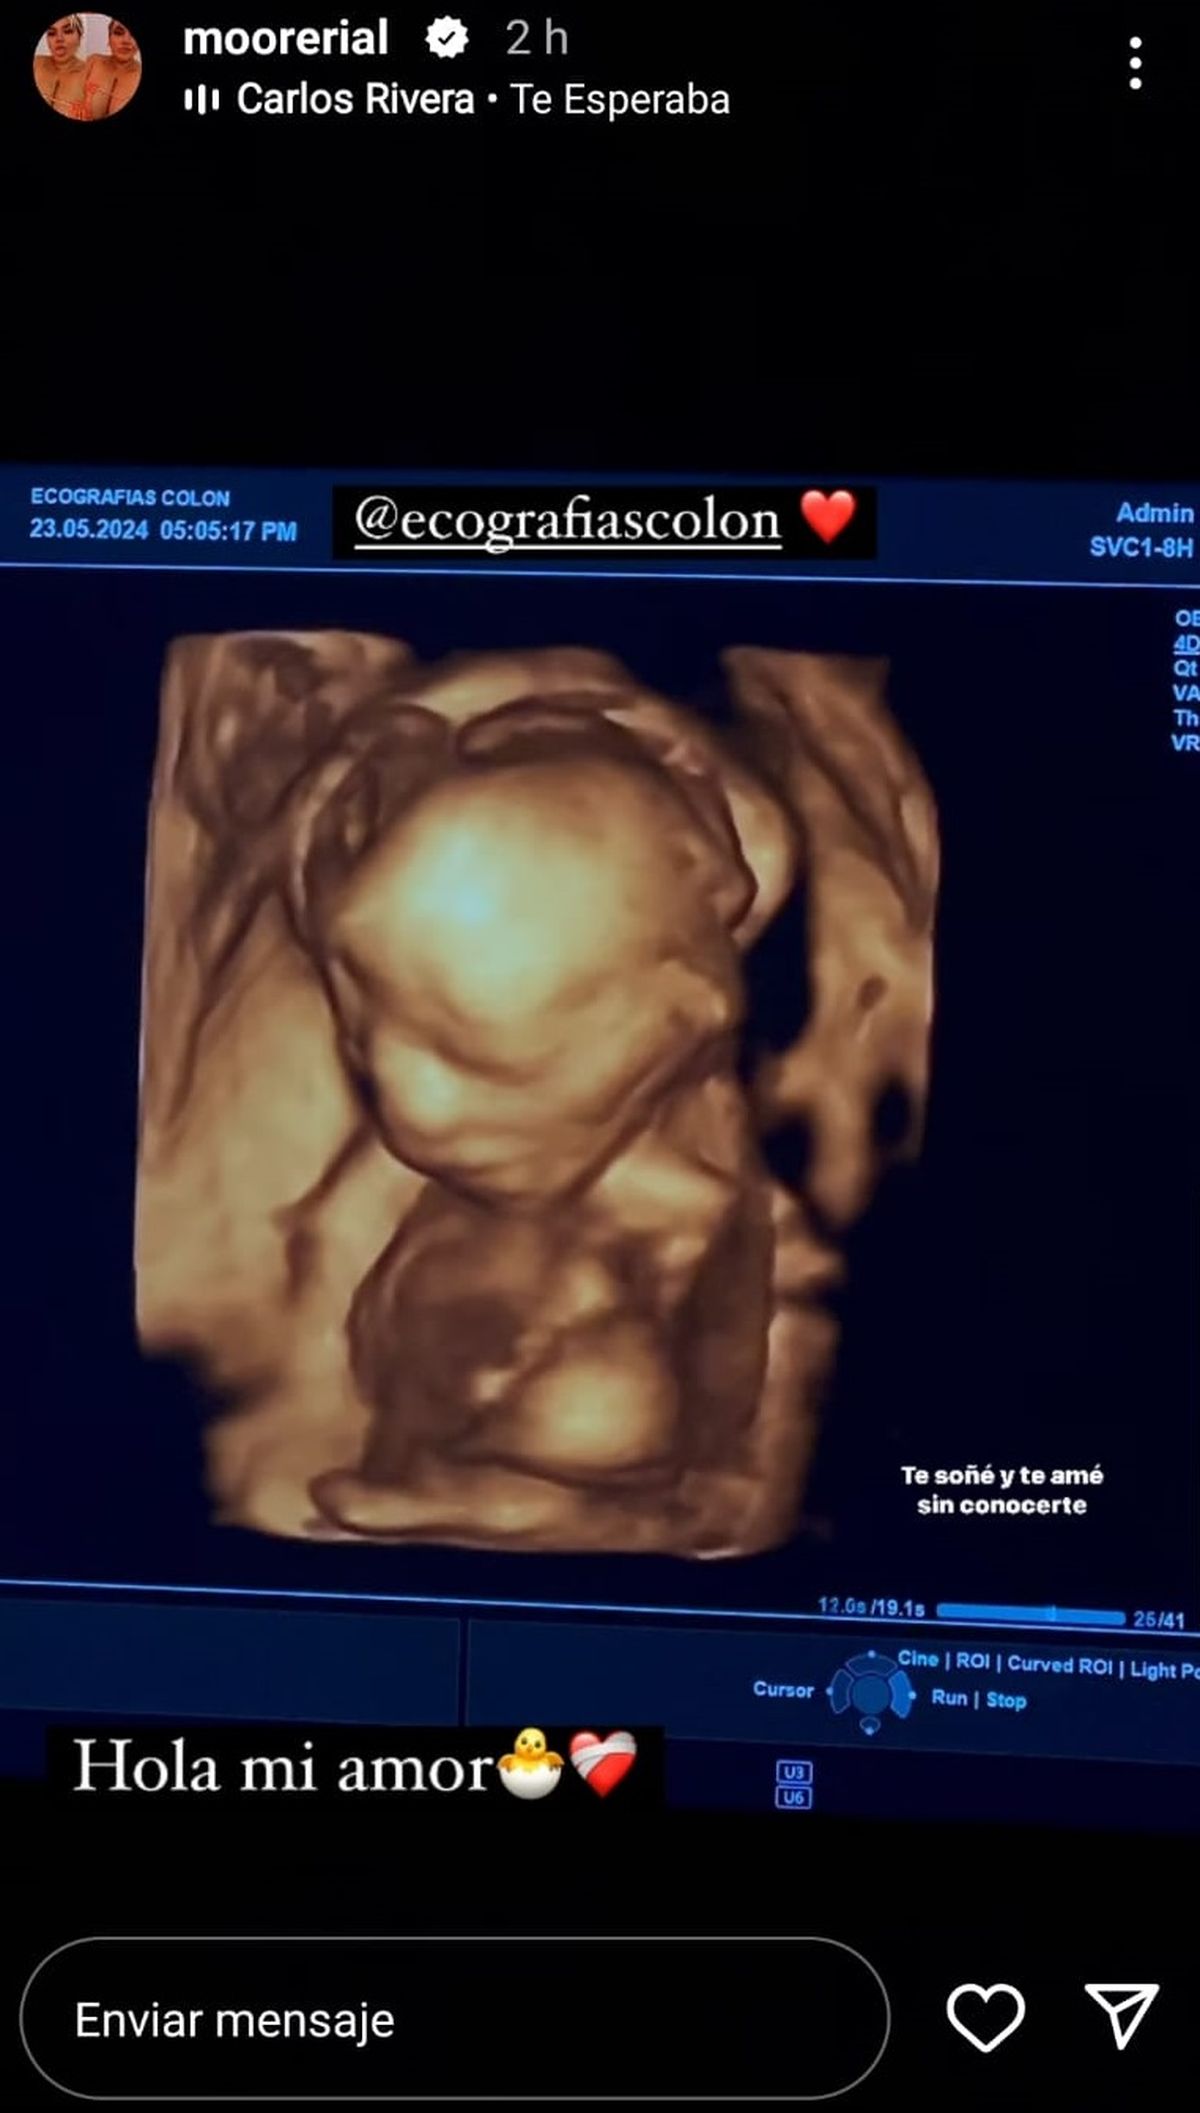

Morena Rial recuperó la cuenta de Instagram en la que tiene casi un millón y medio de seguidores y lo celebró publicando una foto de su bebé, fruto de su relación con un boxeador llamado Matías. Se trata de una imagen que corresponde a la ecografía, donde se puede ver la carita de la criatura, de la que ella aún no quiso decir el sexo.

Morena Rial mostró la cara de su bebé ¡y es igualito a ella!

Morena Rial sorprendió a sus seguidores con una foto de su segundo hijo, fruto de su amor con un boxeador.